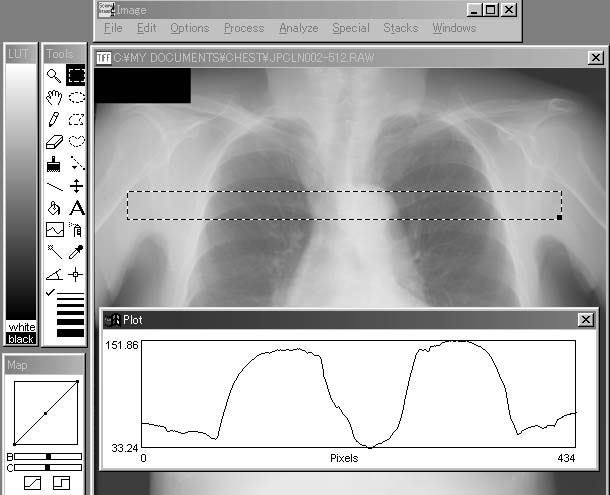

C. Plot Profile(プロファイルの表示)

「Plot Profile」では,領域選択ツールで選択された領域のプロファイルを作成する.ここでは,選択した領域が長方形の場合は(おおむね長方形で領域を選択すると考えられるが),長軸方向にプロファイルの横幅が設定され,反軸方向の画素値の平均が示される(図5-4).この例では,点線で囲われた領域におけるプロファイルを表示している.正方形の場合は,画像の横軸方向がプロファイルの横軸になる.なお,選択した領域を移動してプロファイルを再描画する場合にも,「Plot Profile」を再び選択すればよい.

図5-4 「Plot Profile」による指定領域(点線内)のプロファイルの表示例